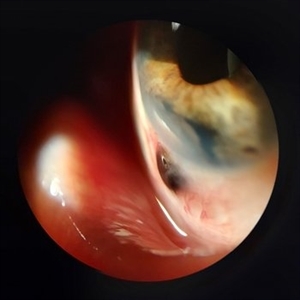

Jan 28 2025 by Korey Starkey

Slit-lamp image of 90-year-old patient with iris melanoma and new hemorrhage affecting the right eye. Patient re-presented after nearly 1 year, now seeking treatment. Given iris location of tumor, multiple clock hours of iris involved, and increase in size of the known malignant transformation; safest approach was enucleation.

Photographer: Korey Starkey

Imaging device: Slit lamp camera

Condition/keywords: anterior chamber, hemorrhage, iris melanoma, slit lamp photo